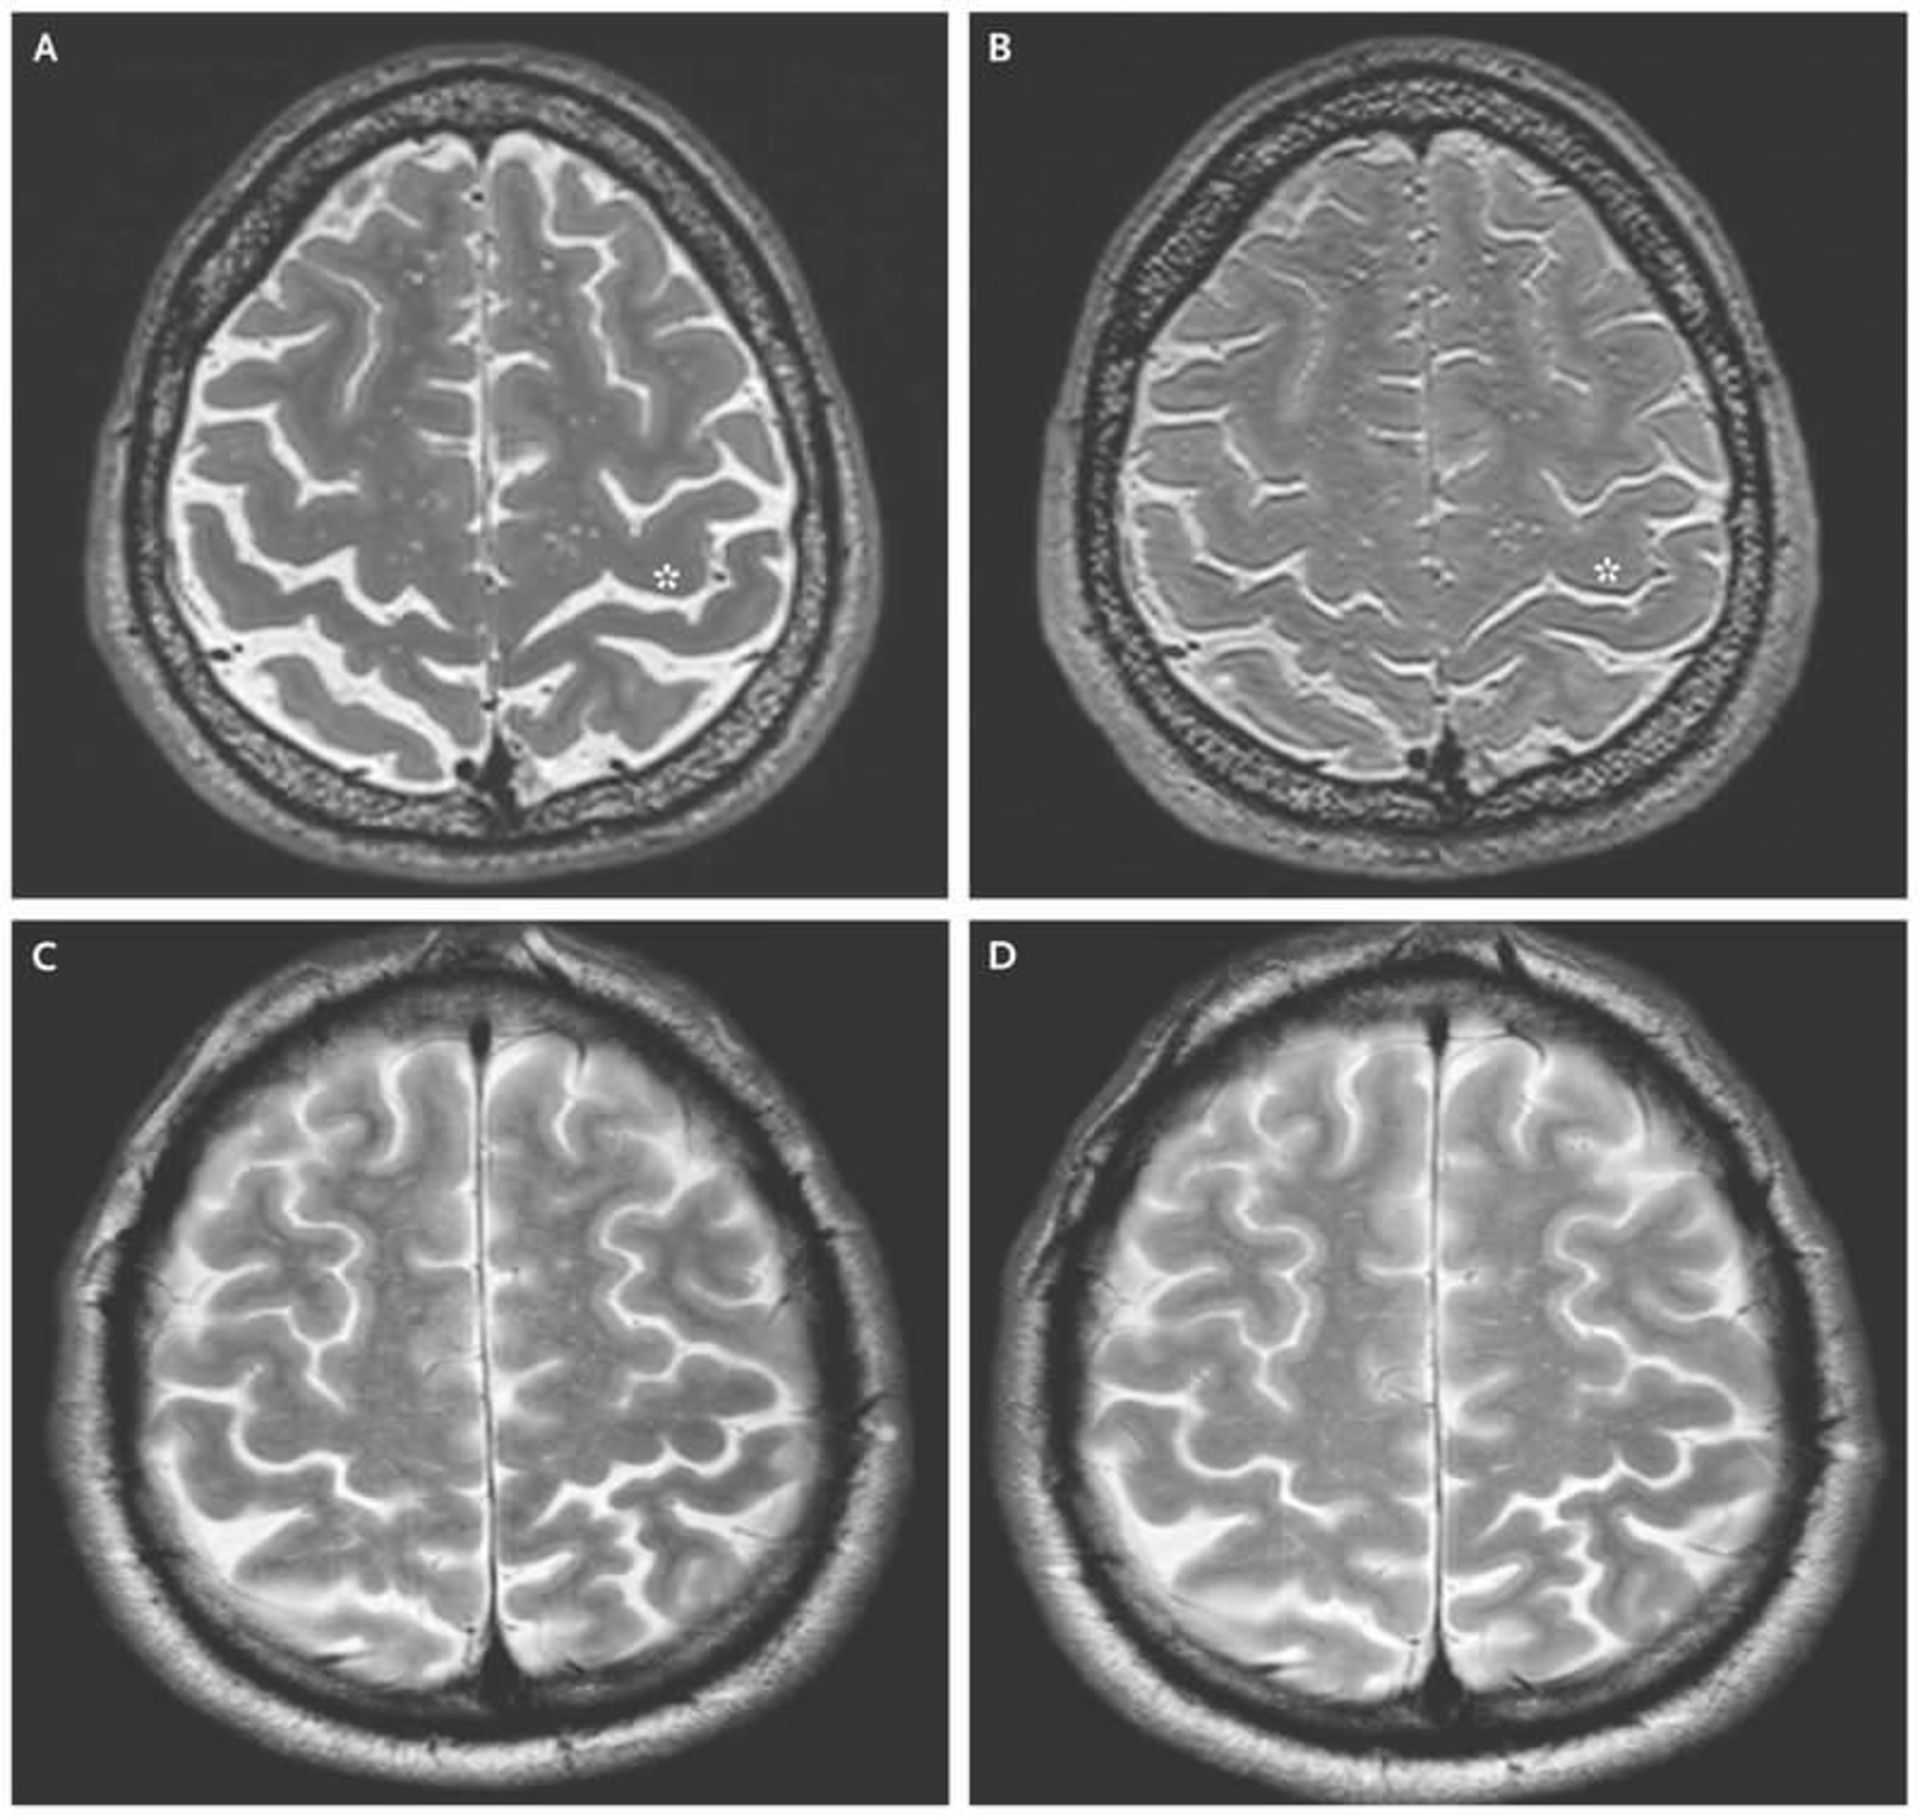

اسکن مغز شرکت‌کنندگان نشان می‌دهد که فضای بین بالای مغز و جمجمه، همانند فضانوردان کاهش پیدا می‌کند

ناسا مطالعه‌ی دیگری در این مورد انجام داده است. ۳۴ فضانورد که در مأموریت‌های فضایی طولانی‌مدت و کوتاه‌مدت ISS یا سفرهای کوتاه‌مدت شاتل فضایی شرکت داشتند، بررسی شدند. مغز هر شخص در مدت کوتاهی قبل و بعد از مأموریت‌ با تکنولوژی fMRI اسکن شد. از ۱۸ فضانورد ISS که به‌عنوان ساکنین طولانی‌مدت فضا طبقه‌بندی شده بودند، ۱۷ نفر علائم تنگ شدن قشر مرکزی مغز نشان دادند. این اتفاق فقط در سه نفر از ساکنین کوتاه‌مدت مشاهده شد. این قشر،  مناطقی از مغز را که مسئول کنترل حرکتی هستند از مناطق مربوط به گیرنده‌های حسی جدا می‌کند.

اسکن مغز فضانوردان / Astronauts Brain Scan

اما رابرتز برای اینکه متوجه شود این اثرات در فضانوردان هم اتفاق افتاده است یا خیر، تصاویر مغز شرکت‌کنندگان را با اسکن‌های مغزی فضانوردان که در موقعیت‌های مختلف گرفته شده بود، مقایسه کرد. در این مقایسه، فضانوردان هم تنگ شدن قشر مرکزی را تجربه می‌کنند؛ بخشی در بالای مغز که لوب‌های پیشانی و لوب‌های آهیانه‌‌ای را از یکدیگر جدا می‌کند. ۹۴ درصد از فضانوردان که سفرهای طولانی‌مدت را سپری کرده‌اند، در این وضعیت بودند و کمتر از ۲۰ درصد از فضانوردانی که از پروازهای فضایی کوتاه‌مدت بازگشته بودند نیز این علائم را نشان دادند.

در ۱۲ نفر از فضانوردانی که حضور طولانی‌مدت در فضا داشتند، مغز، حرکتی کلی به سمت بالای جمجمه داشت. همچنین کانال‌های مغزی-نخاعی در بالای جمجمه‌ی ۱۲ نفر از این فضانوردان ‌و یک نفر از فضانوردانی که حضور کوتاه‌مدت داشتند، کوچک شده بود. دانشمندان هنوز مطمئن نیستند این باریک شدن چه تأثیری دارد، آیا مانع از جریان مایع مغزی-نخاعی می‌شود یا بافت‌های اطراف را تحت فشار قرار می‌دهد؟ یک راه حل مناسب برای کاهش اثرات زندگی در فضا روی مغز و همچنین از بین بردن علائم VIIP، این است که مایع نخاعی را که از فشار موجود تولید می‌شود، خارج کرد. اما در حال حاضر، هیچ روشی برای انجام این کار پیچیده‌ای در فضا وجود ندارد.